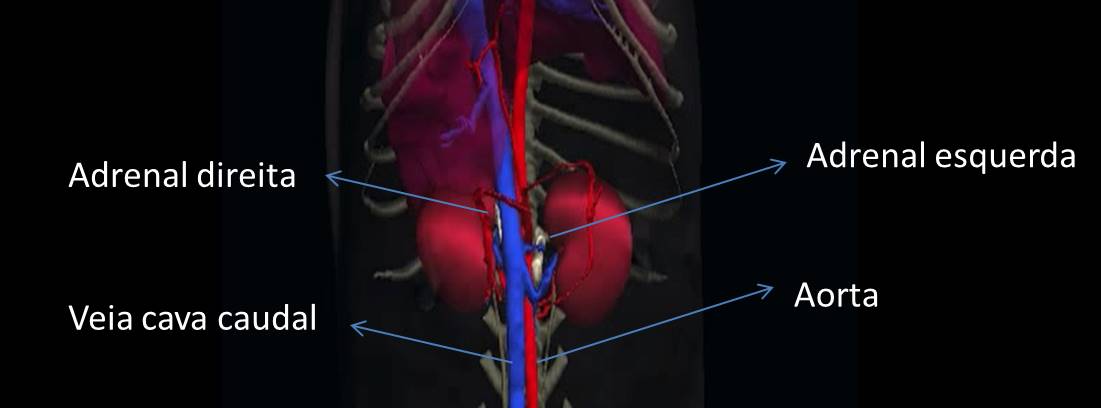

Essas glândulas podem ser avaliadas durante o exame ultrassonográfico. A adrenal esquerda é mais fácil de se encontrar porque está um pouco mais caudal que a direita. O conhecimento da sua posição anatômica nos ajuda na hora do exame. Ela fica entre o rim esquerdo e a aorta, caudal às arterias celíaca e mesentérica cranial, cranial à artéria renal. Já a glândula adrenal direita fica cranial às artérias celíaca e mesentérica cranial e justaposta à veia cava caudal.

Glândula adrenal direita e sua proximidade à veia cava caudal.